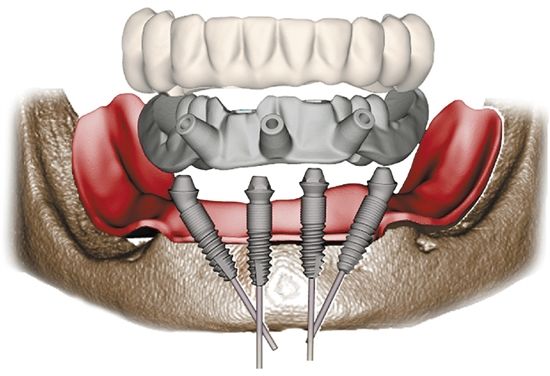

海涛“一天得”全口种植牙技术是海涛口腔的特色技术,该技术对口腔机构数字化水平要求非常高,医生经过CBCT扫描和3-SHAPE口内扫描,就可以准确获取缺牙者牙槽骨精密数据,然后定制数字化导板,这就好比生活中用的定位导航一样,确保手术过程中将种植体植入术前所精心设计的准确位置,以此来保障患者戴冠后能得到媲美真牙的咀嚼能力。

海涛口腔种植科唐主任介绍,海涛“一天得”全口种植牙技术不仅最大程度地减轻了种牙创伤,快速恢复口腔美观与功能,更是打破了传统种植因骨量不足难以种植的缺点,同时,在海涛口腔数字化技工的支持下,实现了当天种牙,当天佩戴义齿,当天吃肉的出色效果。此外,由于海涛“一天得”全口种植牙仅需植入4-6颗种植体就可解决半口无牙问题,加之无需植骨,在费用上也相比传统种植省了一大半。